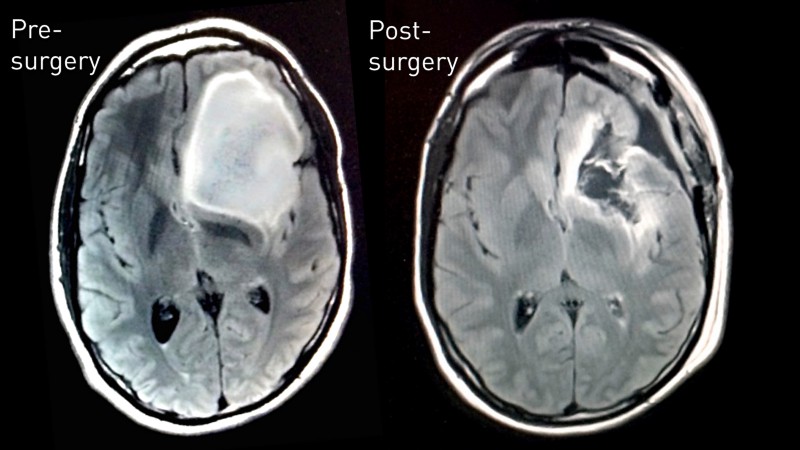

Его коллекция вскоре пополнилась 40-терапиксельным изображением ткани опухоли, расшифровкой генома, МРТ-сканами до и после операции, анализами микробиома до и после химиотерапии и видео высокого разрешения с компьютерной томографией его зашитого черепа – более 200 Гб данных, доступных публично.